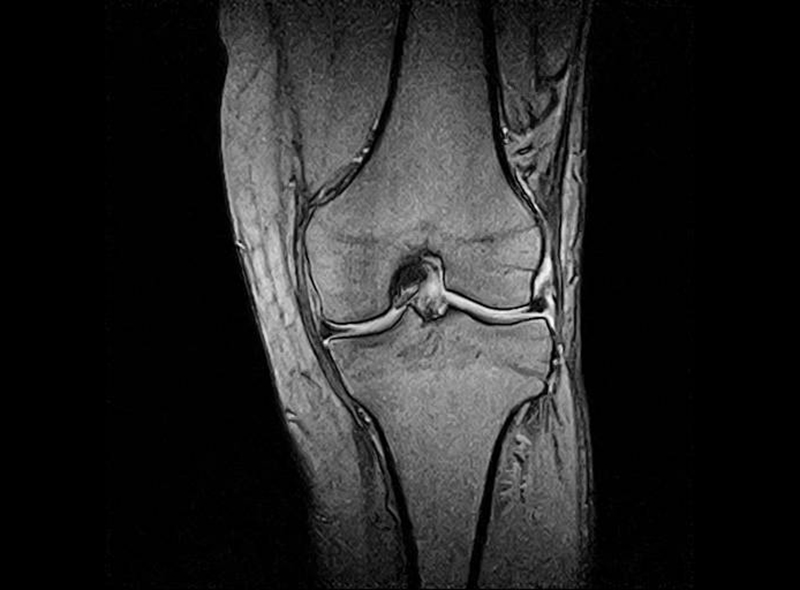

MRI

レントゲンでは判別困難な筋肉、靭帯などの軟部組織や微少骨折などの診断が放射線の被曝無しに行えるため安全で正確な検査が可能です。

当院の機器は開放型MRIであるため検査中の閉塞感が少なくなっています。

膝(半月板損傷)